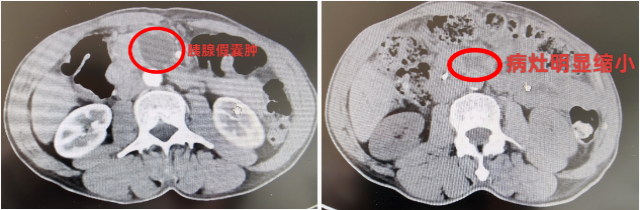

术后第二天,游大爷复查血淀粉酶及脂肪酶均正常,可以正常进食稀饭,不再恶心呕吐,可以四处活动。术后五天,复查腹部CT,见胰头部囊肿明显缩小,游大爷开心地说:“我已经不痛了,吃东西也好多了,没想到手术恢复这么快,解决了我11年的病痛!”

术前CT 术后CT